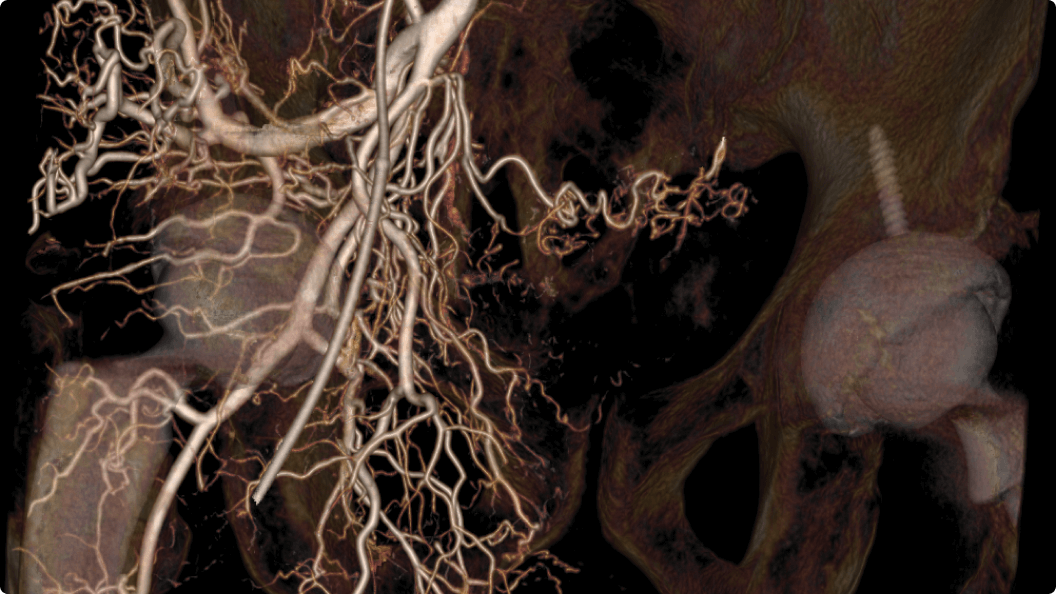

3D CT HD5

Optimierung von Diagnosen, chirurgischen Planungen, interventionellen Verfahren und Nachfolgeuntersuchungen

3D CT HD5 ist eine Option, die auf fortschrittlichen Algorithmen basiert. Diese Algorithmen verbessern die Visualisierung von Weichgewebe, reduzieren Rauschen und minimieren Artefakte, die den Visualisierungskomfort beeinträchtigen können. 3D CT HD bietet eine qualitativ hochwertige Bildgebung von internen Körperstrukturen einschließlich Gefäßen, Knochen und Weichgewebe. Mit dieser Funktion können Ärzte auf Aufnahmen von hoher Qualität zugreifen und fundierte Entscheidungen treffen.

3D CT HD5: Enhanced soft-tissue visualization and noise reduction for high-quality CBCT imaging